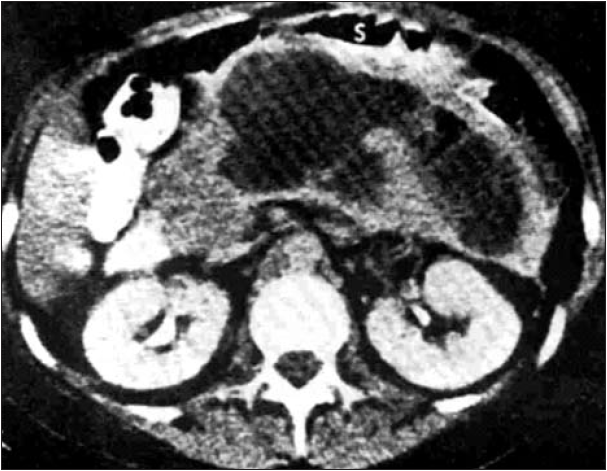

Except for the epigastric mass, the physical examination was quasi-normal. Laboratory data, such as hemoglobin, hematocrit, blood urea, creatinine, serum amylase and the coagulation profile, ranged between normal values. The abdominal contrast-enhanced computed tomography revealed a fluid collection with well-defined walls, at the level of the body and tail of the pancreas which was initially classified as pancreatic pseudocyst, because information about the morphologic type of acute pancreatitis was lacking – either interstitial or acute necrotizing pancreatitis (Fig. 1). Both transabdominal and endoscopic ultrasonographic evaluations indicated viscous content, the fluid collection corresponding to a WON, and the gastroenterologist who performed the procedure considered it ineligible for endoscopic internal drainage.

Figure 1.

Contrast-enhanced computed tomography image of pancreatic walled-off necrosis (WON) at the level of the body and tail of the pancreas